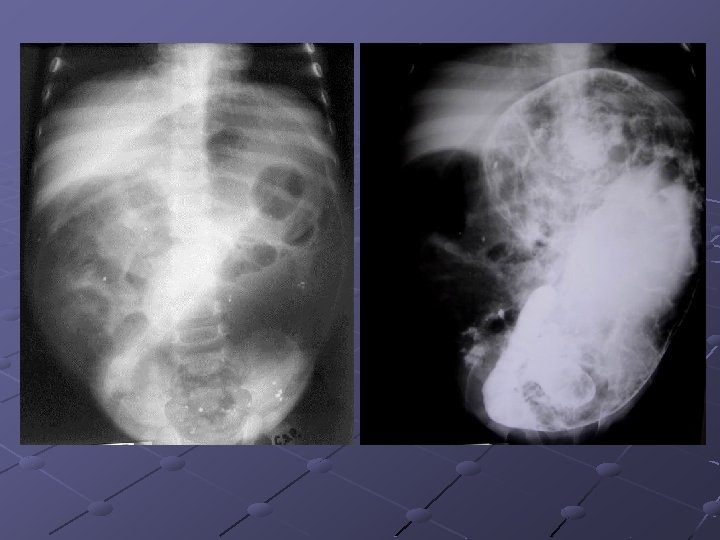

Cas n° 5 17 mois Histoire médicale antérieure = o Pleurs, douleurs abdominales

3, 7 x 2, 8 cm Depuis le rectum hypochondre gauche

INVAGINATION INTESTINALE AIGUE (IIA) Télescopage et penetration d’ un segment intestinal dans le segment d’ aval. Urgence diagnostique et thérapeutique: compression vasculaire ischémie et nécrose Nourrisson ( 80 % entre 6 mois et 2 ans ). Maximum entre 4 et 12 mois (I). Avant 3 mois ou après 5 ans (II). Prédominance masculine ( 3 G/2 F).

Idiopathique ( 90% des cas ): adénolymphite mésentérique(caractère saisonnier ) Secondaire: lymphome digestif, meckel, duplication digestive , polype , purpura rhumatoïde , troubles fonctionnels post chirurgicaux , impactions digestives ( mucoviscidose. . ) Formes anatomiques: iléo-iléale n iléo-colique n Appendico-colique n colo-colique n diam. boudin < 20 mm diam. boudin > 25 mm Diagnostic = échographie et non l’ASP Traitement: - Lavements (air, hydrosoluble, eau) - Chirurgie Contre-indications des lavements: péritonite, choc